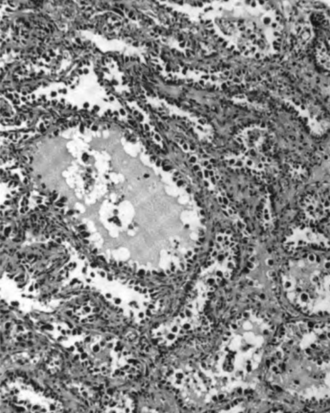

Serous ovarian cancer is the most common type of epithelial ovarian cancer and it accounts for about two-thirds of cases of epithelial ovarian cancer.[28] Low-grade serous carcinoma is less aggressive than high-grade serous carcinomas, though it does not typically respond well to chemotherapy or hormonal treatments.[28] Serous carcinomas are thought to begin in the Fallopian tube.[68][69] High grade serous carcinoma accounts for 75% of all epithelial ovarian cancer.[67] About 15–20% of high grade serous carcinoma have germline BRCA1 and BRCA2 mutations.[67] Histologically, the growth pattern of high grade serous carcinoma is heterogenous and has some papillary or solid growth patterns.[67] The tumor cells are atypical with large, irregular nuclei.[67] It has a high proliferation rate.[67] 50% of the time, serous carcinomas are bilateral, and in 85% of cases, they have spread beyond the ovary at the time of diagnosis.[70]

Serous Tubal Intraepithelial Carcinoma (STIC) is now recognized to be the precursor lesion of most so-called ovarian high-grade serous carcinomas.[70] STIC is characterised by